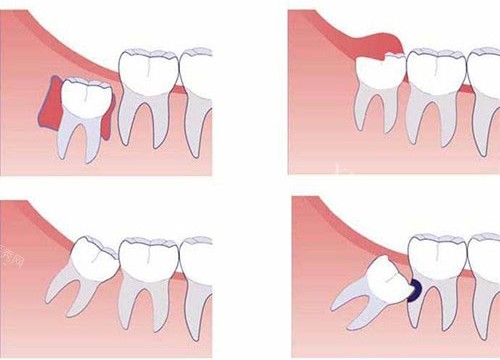

2. 阻生智齿(700-2500元起)

垂直阻生:600-1500元起

需切开牙龈暴露牙冠,手术时间约30分钟。某连锁品牌对垂直阻生智齿收费1000-1500元起。

水平阻生/倒置阻生:1500-2500元起

需去骨分牙的复杂手术,某综合医院口腔科对完全埋伏的水平阻生智齿收费可达2200起元。

特殊病例:

天津某高端诊所对"下颌近中阻生智齿(牙冠紧贴邻牙)"采用超声骨刀小创口技术,收费高达2500元,但术后肿胀率降低60%。